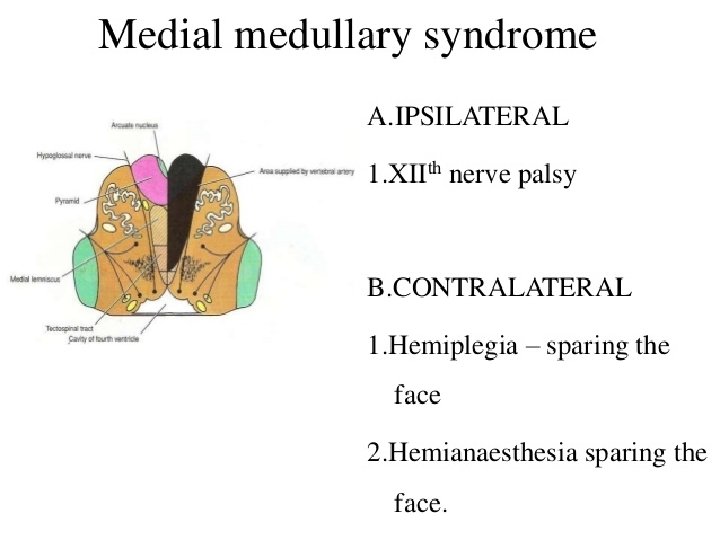

LATERAL MEDULLARY SYNDROME • Also called posterior inferior cerebellar artery (PICA) thrombosis and Wallenberg’s syndrome) • Acommon example of brainstem infarction presenting as acute vertigo with cerebellar and other signs. It follows • Thromboembolism in the PICA or its branches, vertebral artery thromboembolism or dissection. • Features depend on the precise structures damaged. MEDIAL MEDULLARY SYNDROME • Characterized by a set of clinical features resulting from occlusion of the anterior spinal artery. This results in the infarction of medial part of the medulla oblongata.

Localization of Lesion Midbrain: CROSSED HEMIPLEGIA: Ø 3 rd /4 th CN are involved on one side and hemiplegia of opposite side Pons: Ø 5 th, 6 th, 7 th and 8 th CN nuclei are present in pons. Ø One or more of these CNs are paralyzed on one side and hemiplegia is on the other side. Ø Pupils are pinpoint but reactive to light Ø Hyperpyrexia may be present Medulla Oblongata: Ø 9 th, 10 th, 11 th and 12 th CN nuclei are present in medulla. Ø One or more of these CNs are paralyzed on one side and hemiplegia is on the other side.